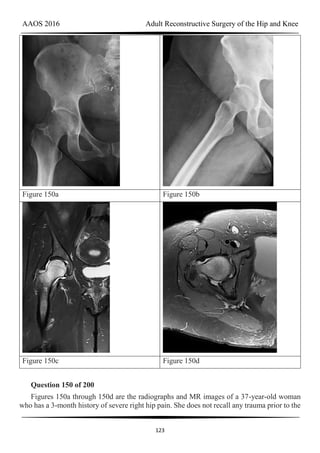

Figure 30a

Question 30 of 200

Figure 30a is the anteroposterior radiograph of a 20-year-old woman with mild right groin

pain and intermittent “catching” in the hip region. What is the most appropriate next step?

AAOS 2016 Adult Reconstructive Surgery of the Hip and Knee

26

1- Arthroscopic evaluation and treatment of the hypertrophic labrum and a possible labral

tear

2- A hip injection to confirm an intra-articular source of the pain

3- Nonsurgical treatment and subsequent total hip arthroplasty (THA) when the patient is

sufficiently symptomatic

4- Periacetabular osteotomy

PREFERRED RESPONSE: 4- Periacetabular osteotomy

DISCUSSION

Because this patient is young, substantial bilateral acetabular dysplasia is present, and the

joint space is well preserved, periacetabular osteotomy is the treatment of choice (Figure 30b).

Arthroscopic evaluation and treatment is insufficient to address the mechanical deformity.

Although a hip injection can be diagnostically helpful, it would not alter the treatment plan in

this scenario. The patient’s young age would make observation and subsequent THA less

desirable. Femoral osteotomies also were performed to address rotational deformity.

Figure 31